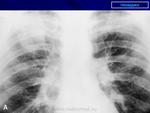

Двусторонняя интерстициальная. Гипертрофия правого корня, перисциссурит малой щели справа. Как бы не вылез центральный справа с лимфогенными метастазами.

Раковый лимфангит скорее всего

возможен чаще всего у человека пожилого возраста. Возраст пациента не указан. Сходную картину может дать саркоидоз органов дыхания II. Диагноз за клиницистами с учетом всех результатов обследования. При интерстициальных заболеваниях легких показазано КТ-исследование, если имеется такая возможность.

Выскажусь, как и в параллельной ветке, за диссеминированный туберкулез. Наверное, здесь можно предположить казеозный очаг (л/у?).

доктора Дмитрия Волегова. Диссеминированному туберкулезу лимфогенного генеза не противоречит преимущественная локализация очагов в средних и нижних отделах легких, особенно у больных с наличием Вич-инфекции.

Не поддержу версию туберкулёза.У ВИЧ-инфецированных она симметрична,как правило.

Если КТ под рукой есть, то лучше не тянуть время.. Изменения явно интерстициальные, на простую пневмонию никак не тянут. Было несколько пациентов с раковым лимфангитом - выглядело это все именно так как на этой ФЛГ

+1. Пнемония как уже сказано, интерстициальная. В дифференциально-диагностический ряд можно выставить и раковый лимфангаит, оздачить клиницистов, но как-то в этом плане не очень убедительно.

Возраст пациента весьма пожилой, в районе 60 лет.

Температура у пациента в течение двух недель в районе 37 с небольшим, только сегодня назначены антибиотики.

В пользу лимфангита еще преимущественное распространение в средних и нижних отделах, неструктурные корни, еще cuffing (разбухание?) стенки бронхов, подчеркнутость междолевых щелей (на боковом хорошо видно, средняя доля "выделена")